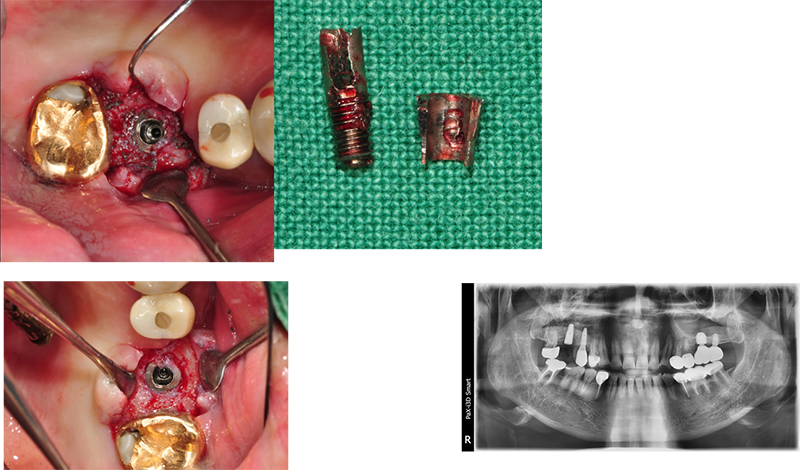

ÇȽºÃĵµ Âõ¾îÁú ¼ö ÀÖ°í, ¾î¹þ¸ÕÆ®µµ ºÎ·¯Áú ¼ö ÀÖ´Ù. ¶ÇÇÑ ³ª»ç Ç®¸²µµ ¸¹ÀÌ ¹ß»ýÇÑ´Ù. ÀÌ·± Ưº°ÇÑ °æ¿ì¿¡µµ EZC¿Í °°Àº convertible abutment°¡ À¯¸®ÇÏ´Ù.

Ext. type 3.75mm Á÷°æÀÇ ÀÓÇöõÆ®.

Bruxism ÀÌ Àִ ȯÀÚ·Î½á ½É°í ±â´ÉÇÑ Áö 15³â ¸¸¿¡ ºÎ·¯Á®¼ ³»¿øÇß´Ù.

Á÷°æÀÌ 3.75mm·Î ¿¹Àü regular¿¡ ÇØ´çÇÏÁö¸¸ 4.0mmº¸´Ù ºÎ·¯Áö´Â °æ¿ì°¡ ¸¹´Ù.

¶ÇÇÑ ExtÀº º¸Ã¶ÀÌ ¿Ã¶ó°¡¸é Ç÷§Æû¿¡¼ 1.5mm °ñÈí¼ö°¡ °ÅÀÇ ÇÊ¿¬ÀûÀ¸·Î ÀϾÙ. À̹ø °æ¿ìµµ °ñÈí¼ö¿Í ±íÀº ¿¬°üÀÌ ÀÖ´Ù°í ¿©°ÜÁø´Ù.

Sub typeÀº ÇȽºÃÄ Á÷°æ°ú´Â º° °³·Î ¾î¹þÀº ¸ðµÎ µ¿ÀÏÇÑ »çÀÌÁî´Ù. Ư¡ÀÌÀÚ ÀåÁ¡ÀÌ´Ù. ÇȽºÃİ¡ ºÎ·¯ÁöÁö ¾Ê¾Æ¼ ´ÙÇàÀÌ´Ù. ±×·¯³ª ¾î¹þÀÇ ¹Øµ¿ÀÌ ºÎ·¯Áø °Íµµ ¸Å¿ì Å« ÇÕº´ÁõÀÌ´Ù. ºÎ·¯Áø ¹Øµ¿À» ±ú²ýÇÏ°Ô »©³»´Â °Íµµ »ó´çÈ÷ Èûµç ÀÏÀÌ´Ù.